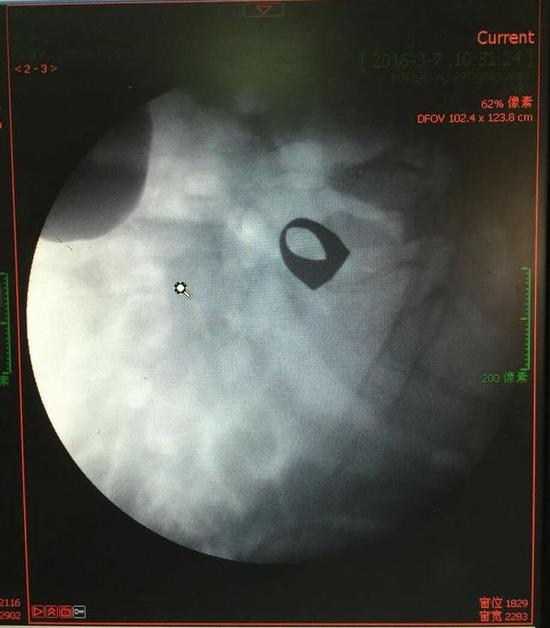

考慮到患者年齡較大,有冠心病,曾經(jīng)中過(guò)風(fēng),高血壓極高危級(jí),遂把老人安排在帶有監(jiān)護(hù)的病房,立即給予吸氧,補(bǔ)液等治療。醫(yī)院立刻開(kāi)啟綠色通道,醫(yī)護(hù)人員專(zhuān)門(mén)陪伴病人做了增強(qiáng)CT,腹部平片,和碘水造影,確定戒指的位置。檢查結(jié)果提示戒指位于右下腹小腸內(nèi),距回盲瓣體表投影約5cm。

3月9日,夏澤鋒教授細(xì)心的給病人做結(jié)腸鏡檢查,找到回盲瓣,調(diào)整結(jié)腸鏡鏡頭,快速的進(jìn)入小腸。結(jié)腸鏡緩緩上行至距離回盲瓣5cm的小腸,沒(méi)有戒指。繼續(xù)上行,至20cm的地方,仍然沒(méi)有找到戒指。

此時(shí)一個(gè)又一個(gè)大大的疑問(wèn)出現(xiàn)在每個(gè)在場(chǎng)的醫(yī)護(hù)人員腦海中,戒指還在小腸里嗎?戒指在哪個(gè)位置呢?夏教授立刻聯(lián)系放射科,拍片子,發(fā)現(xiàn)戒指已經(jīng)移動(dòng)了,從右側(cè)移動(dòng)到了左側(cè)去了。放射科醫(yī)師建議,戒指有可能會(huì)繼續(xù)沿腸道下行,如果過(guò)了回盲瓣,就可以自行排出,免除手術(shù)痛苦。教授們采納了這個(gè)意見(jiàn),立即給予促進(jìn)胃腸道動(dòng)力藥,枸櫞酸莫沙必利片,每日口服三次,另外配合灌腸治療,促進(jìn)腸道蠕動(dòng),利于戒指排出。